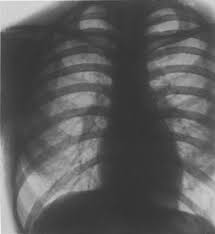

Kaum schwere Spätfolgen für die Lunge

Doch es gibt auch gute Nachrichten. Am Klinikum Stuttgart vergleichen Radiologen in einer Studie derzeit Tomografieaufnahmen der Lungen von 50 Corona-Patienten, während und nach der Infektion. Drei Monate nach Genesung haben ungefähr 20 Prozent der Patienten eine völlig gesunde Lunge. Bei den restlichen 80 Prozent sind zwar immer noch Beeinträchtigungen zu erkennen, doch ist die Rede in der Mehrzahl der Fälle nicht von schweren Spätfolgen, sagt der Leiter der Studie, Götz Martin Richter: Wir können erkennen, dass die Lunge gut heilen kann, auch bei Patienten, die drei Wochen Intensivstation hinter sich haben.

Je nach Schwere der Erkrankung brauche die Lunge mehr oder weniger Zeit, um sich zu regenerieren, erklärt Richter. Das alles seien nur erste Erkenntnisse, denn weltweit laufen derzeit Langzeitstudien zu den Spätfolgen von Corona. Tagesschau.de; von Susett Kleine und Daniel Donath, RBB